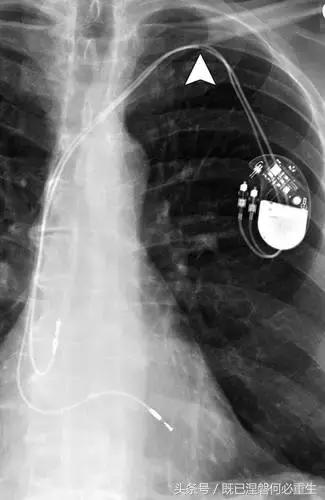

图 1A B 在75岁男性中植入式心律转复除颤器(ICD)的正常部件。

A,额叶胸片显示Medtronic(公司名字)单室ICD。 ICD的基本组件包括发生器,导线和围绕右心室(RV)导线的冲击线圈。 该系统还具有上腔静脉(SVC)中的冲击线圈,其可能不存在于所有系统中。 起搏器没有冲击线圈。 铅固定(见图8A)固定到胸部,并且可能或可能不在胸部X光片上可见。

B,引线通过头连接到发电机(黄色),其保持一个或多个连接端口。 所示系统需要三个端口(一个用于双极起搏或感测元件,一个用于RV休克线圈,一个用于SVC冲击线圈)。 正确放置的引脚将延伸超出连接器(见图9)。 制造商的标志和单个设备标识符的字体被反转,因为发电机被定向以允许在发生器口袋中适当的引线盘绕。 这种定位被设计成减少扭结的风险,这可能导致断裂。 有关制造商徽标的更多信息,请参见图4。